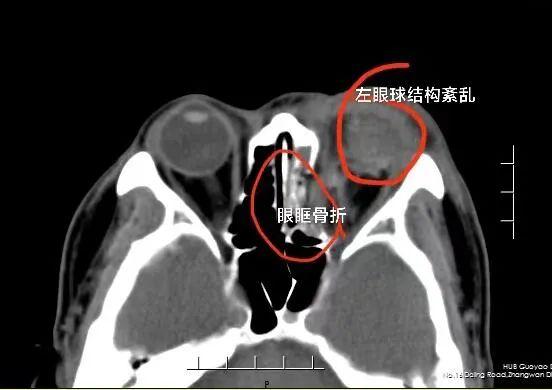

当天,值班的国药东风总医院眼科副主任医师朱峰带领团队对刘先生进行了急诊手术。朱峰在术中发现,患者左侧眉弓处伤口已深达骨面,眼球破裂超过10mm,角膜中央呈花瓣样向多个方向不规则裂伤,眼球由于眼内容的脱失皱缩成了一团。

“眼球破裂,都瘪了,眼睛中有不少碎屑,角膜横径全层裂开,晶体和虹膜脱出,伤口污染重。”朱峰说,刘先生是典型的复杂眼球爆炸伤,前后历经了4个多小时才完成缝合。

朱峰回忆,刘先生被送到医院时,眼睛受伤比较严重,经检查,他的眼镜碎片卡在了眼睛里,角膜到处血迹斑斑,眉毛也被烟花烧没了。“尽管受伤当天已经紧急做了手术,把眼睛的结构修复完整,患者能感受到些许光亮,但由于伤势较重,后期还要进行多次手术治疗。视力丧失的风险较大。”朱峰介绍。